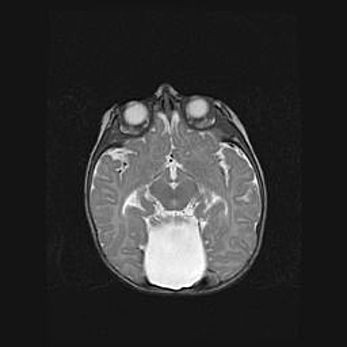

Лейкомаляция с кистозно-глиозной дегенерацией головного мозга.

Возраст: 2 месяца 25 дней

Вес: 6400 г

Окружность головы: 40 см

Срок гестации: 41 неделя

Лейкомаляцию относят к ишемически-гипоксическим повреждениям головного мозга, диагностируемым у новорожденных. При лейкомаляции в головном мозге обнаруживают очаги некроза, возникшие после тяжелой гипоксии и нарушения кровотока. В процессе морфогенеза очаги проходят три стадии: 1) развития некроза, 2) резорбции и 3) формирования глиозного рубца или кисты. Перивентрикулярная лейкомаляция (ПЛ) встречается примерно в 12% случаев среди новорожденных, обычно – у недоношенных детей, причем, частота ее зависит от массы, с которой младенец появился на свет. Наибольшее число малышей страдает лейкомаляцией, если масса при рождении 1500-2500 г.